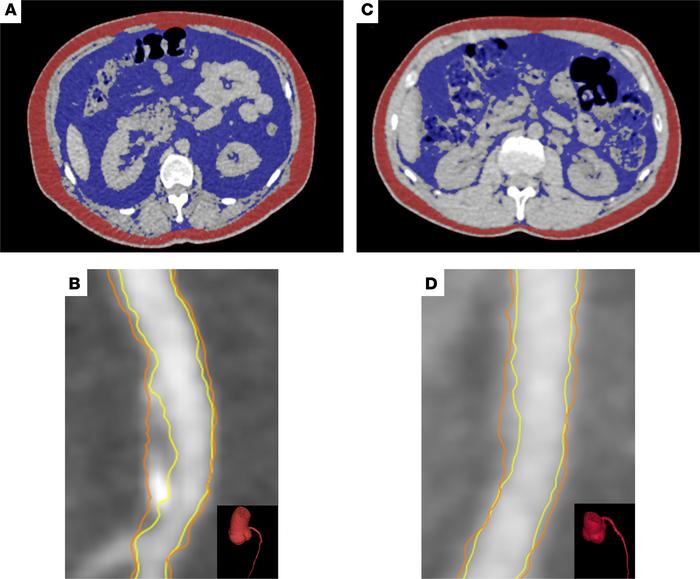

Figure 2

Visceral adiposity and noncalcified coronary artery burden in psoriasis.

(A) Axial abdominal CT of a patient with psoriasis with high VAT volume (VAT, 32,767 cc3) for quantification of visceral (blue) and subcutaneous (red) adiposity. (B) CCTA showing the proximal left anterior descending artery (LAD) of the same patient, with the lumen (yellow) and the outer walls (orange) (LAD noncalcified coronary artery burden, 1.04 mm2) shown. (C) Axial abdominal CT of an age- and sex-matched patient with psoriasis with low VAT (VAT, 13,900 cc3) for quantification of visceral (blue) and subcutaneous (red) adiposity. (D) CCTA showing the LAD of the same patient, with the lumen (yellow) and the outer wall (orange) (LAD noncalcified coronary artery burden: 0.84 mm2) shown.